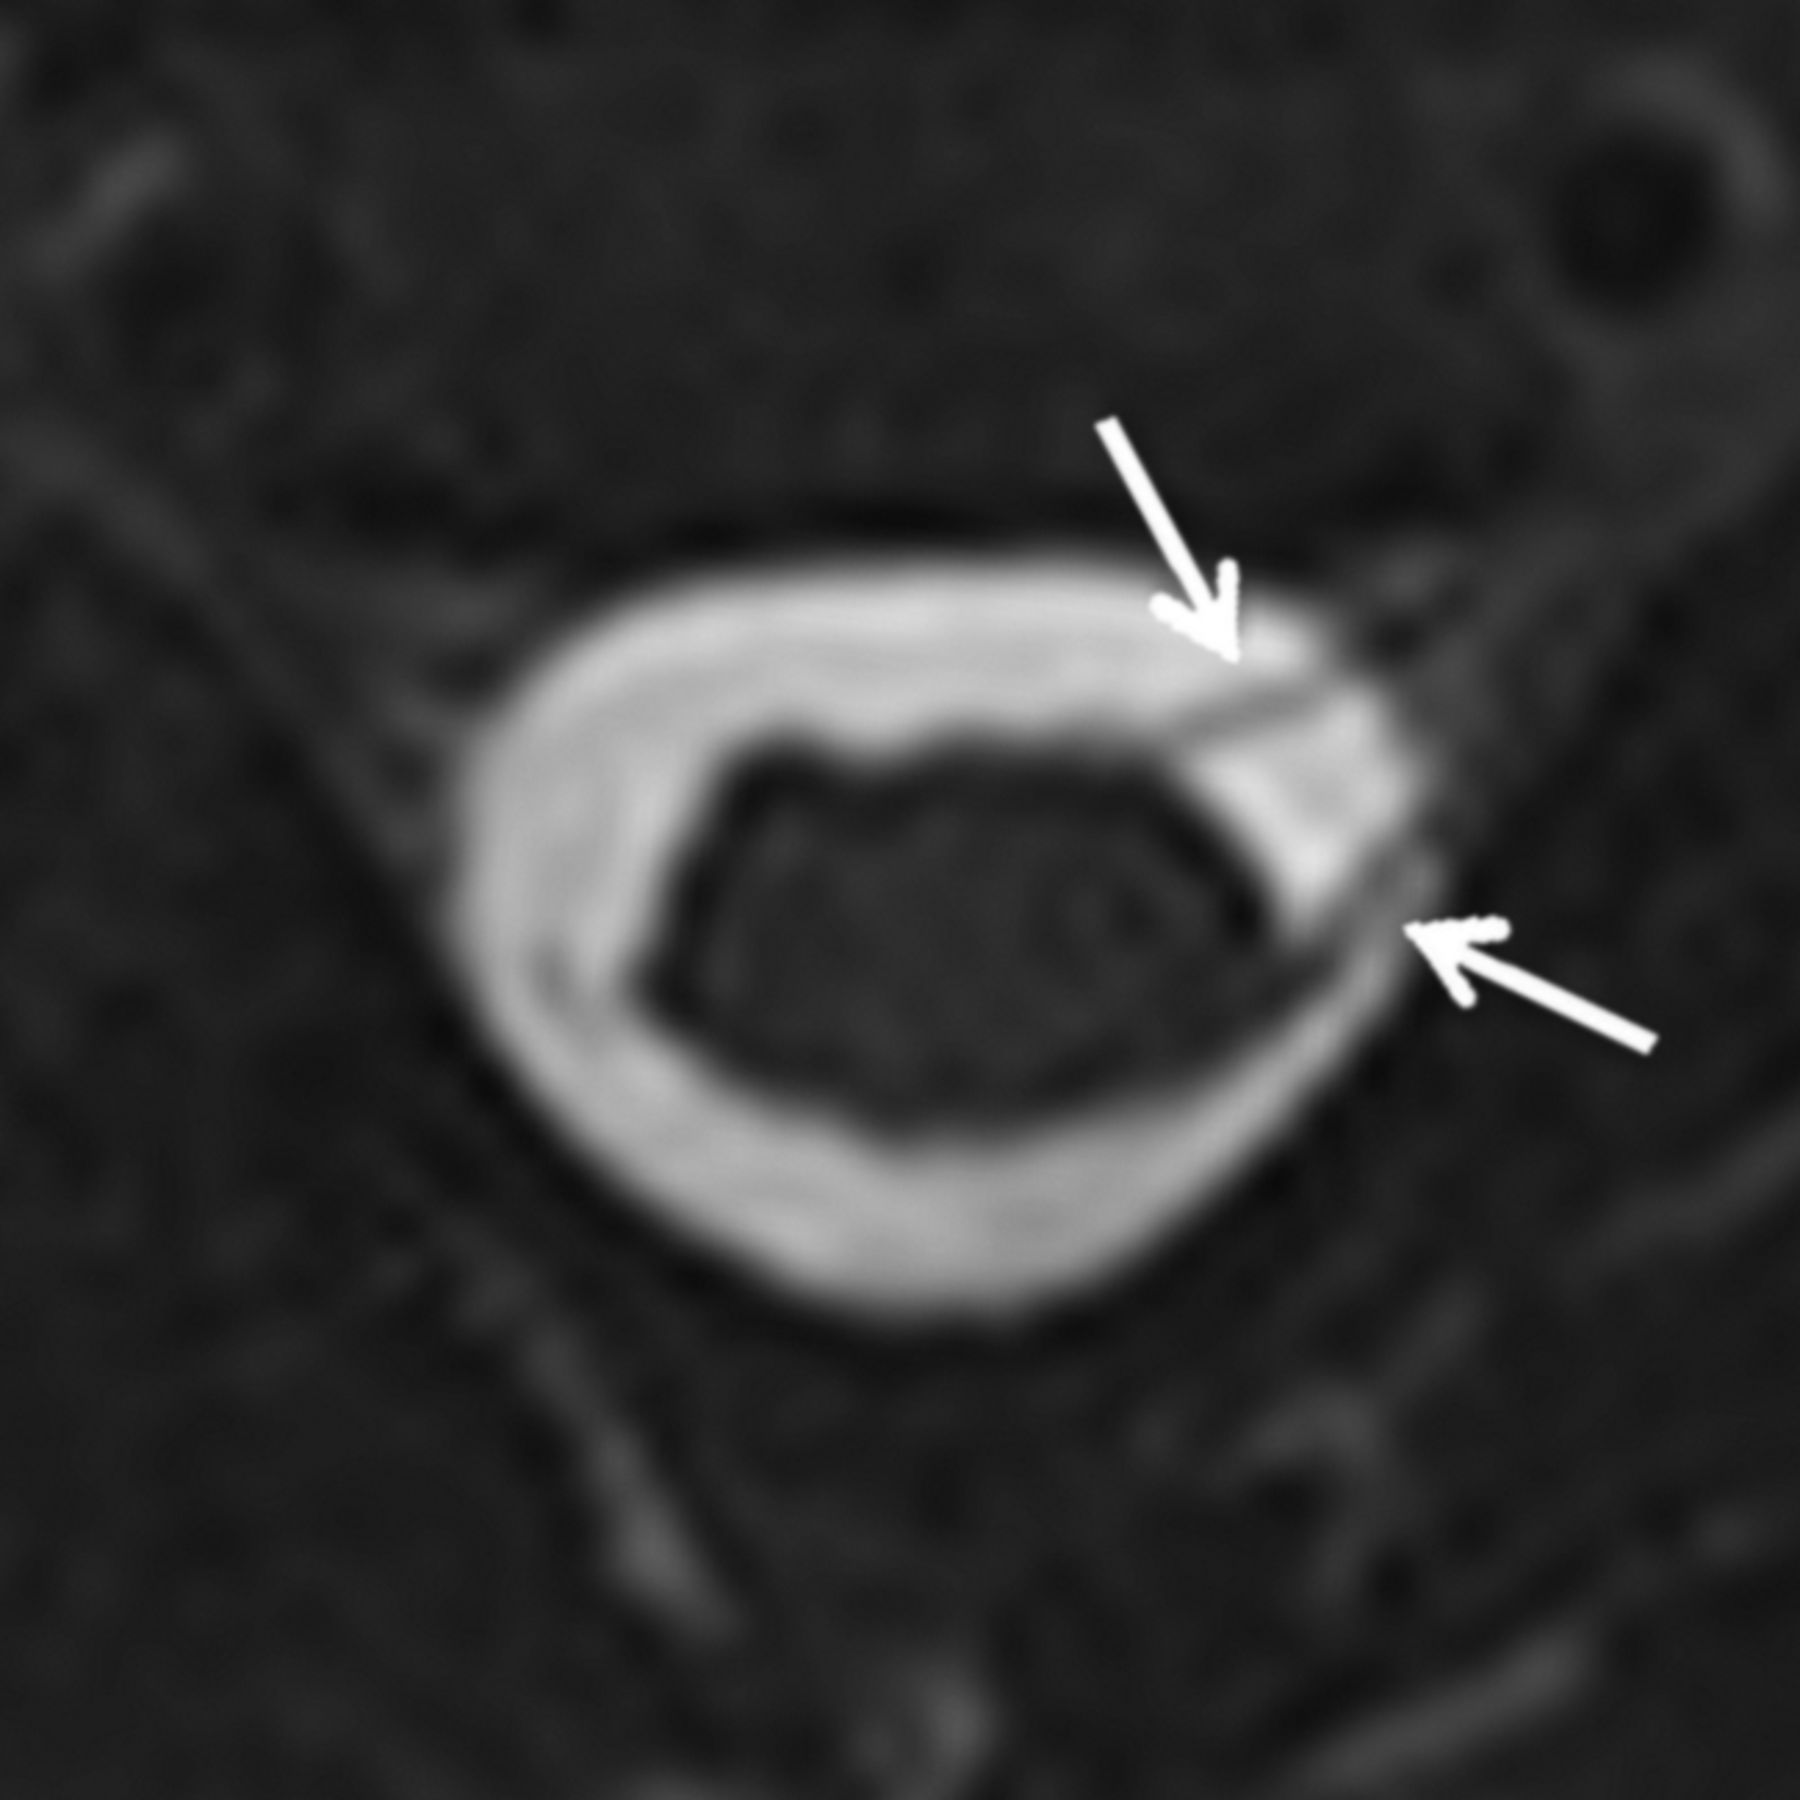

Two pediatric radiologists (with 7 and 8 years' experience, respectively) independently evaluated each imaging study and rated each root level from C5 to T1 according to the system in Table 1. Discrepancies were resolved by consensus analysis. Findings A and B (Figs 1 and 2) have previously been used as predictors of nerve root avulsion in infants.14 Finding C (Fig 3) has been described as a predictor in adults.19 Findings D and E (Figs 4 and 5) have been suggested to indicate partial nerve root avulsion.12

Axial minimum-intensity-projection image from an MR myelogram demonstrating only left-sided rootlets at C5 (arrows), with absent corresponding right-sided rootlets. The base resolution was 0.6-mm isotropic, with a 2-mm minimum-intensity-projection slab.